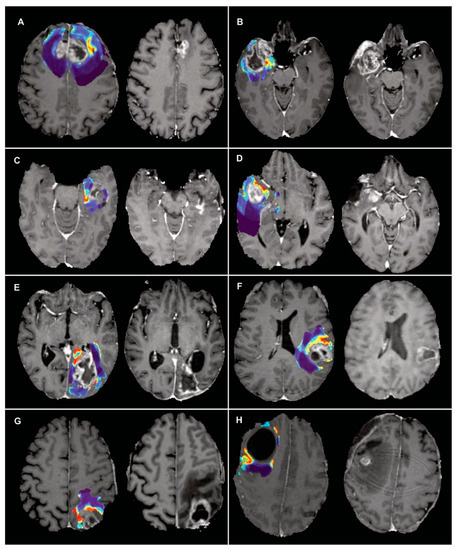

2.6. Probability Maps and Predicted Recurrence Labels

3. Results